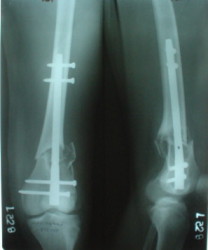

1

Sorry but I've just prepared postop images - attached. A solid 13 mm nail was used. A few degrees of recurvation appears to be which i missed on image intensifier. I'm still uncertain about

advantages/disadvantages of ante/retrograde nailing for such fractures.

The fixation as you have done is excellent. The locking screws on either side of the # are so apart. When we put in a supracondylar nail thro a keyhole incison in the knee, the locking bolts will be nearer the # and will be more stable allowing him to bear wt early. That was the reason the supracondylar nail was innovated. The locking is done by jig and no freehand method saving time.